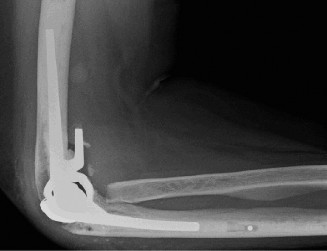

The patient undergoes resection arthroplasty with antibiotic cement spacer and a 6-week course of IV antibiotics. He returns to clinic 4 months later with improved pain, CRP <3, however, on examination he has a positive belly press sign and increased external rotation compared with the contralateral shoulder. Imaging is shown in Figure 2–57.

Figure 2–57

The correct answer is (D). The patient has completed his course of antibiotics and his spacer and is now an appropriate candidate for explanation of the cement spacer with revision shoulder arthroplasty, therefore Choices A and C are incorrect. The patient’s clinical examination findings point to rotator cuff tear (specifically subscapularis) which has occurred in the interval between his obtaining his initial total shoulder arthroplasty and his current examination. Therefore, total shoulder arthroplasty (Choice B) is contraindicated, and the patient should have a reverse total shoulder arthroplasty. Objectives: Did you learn...? Recognize the clinical presentation of a patient with infection after total shoulder arthroplasty?